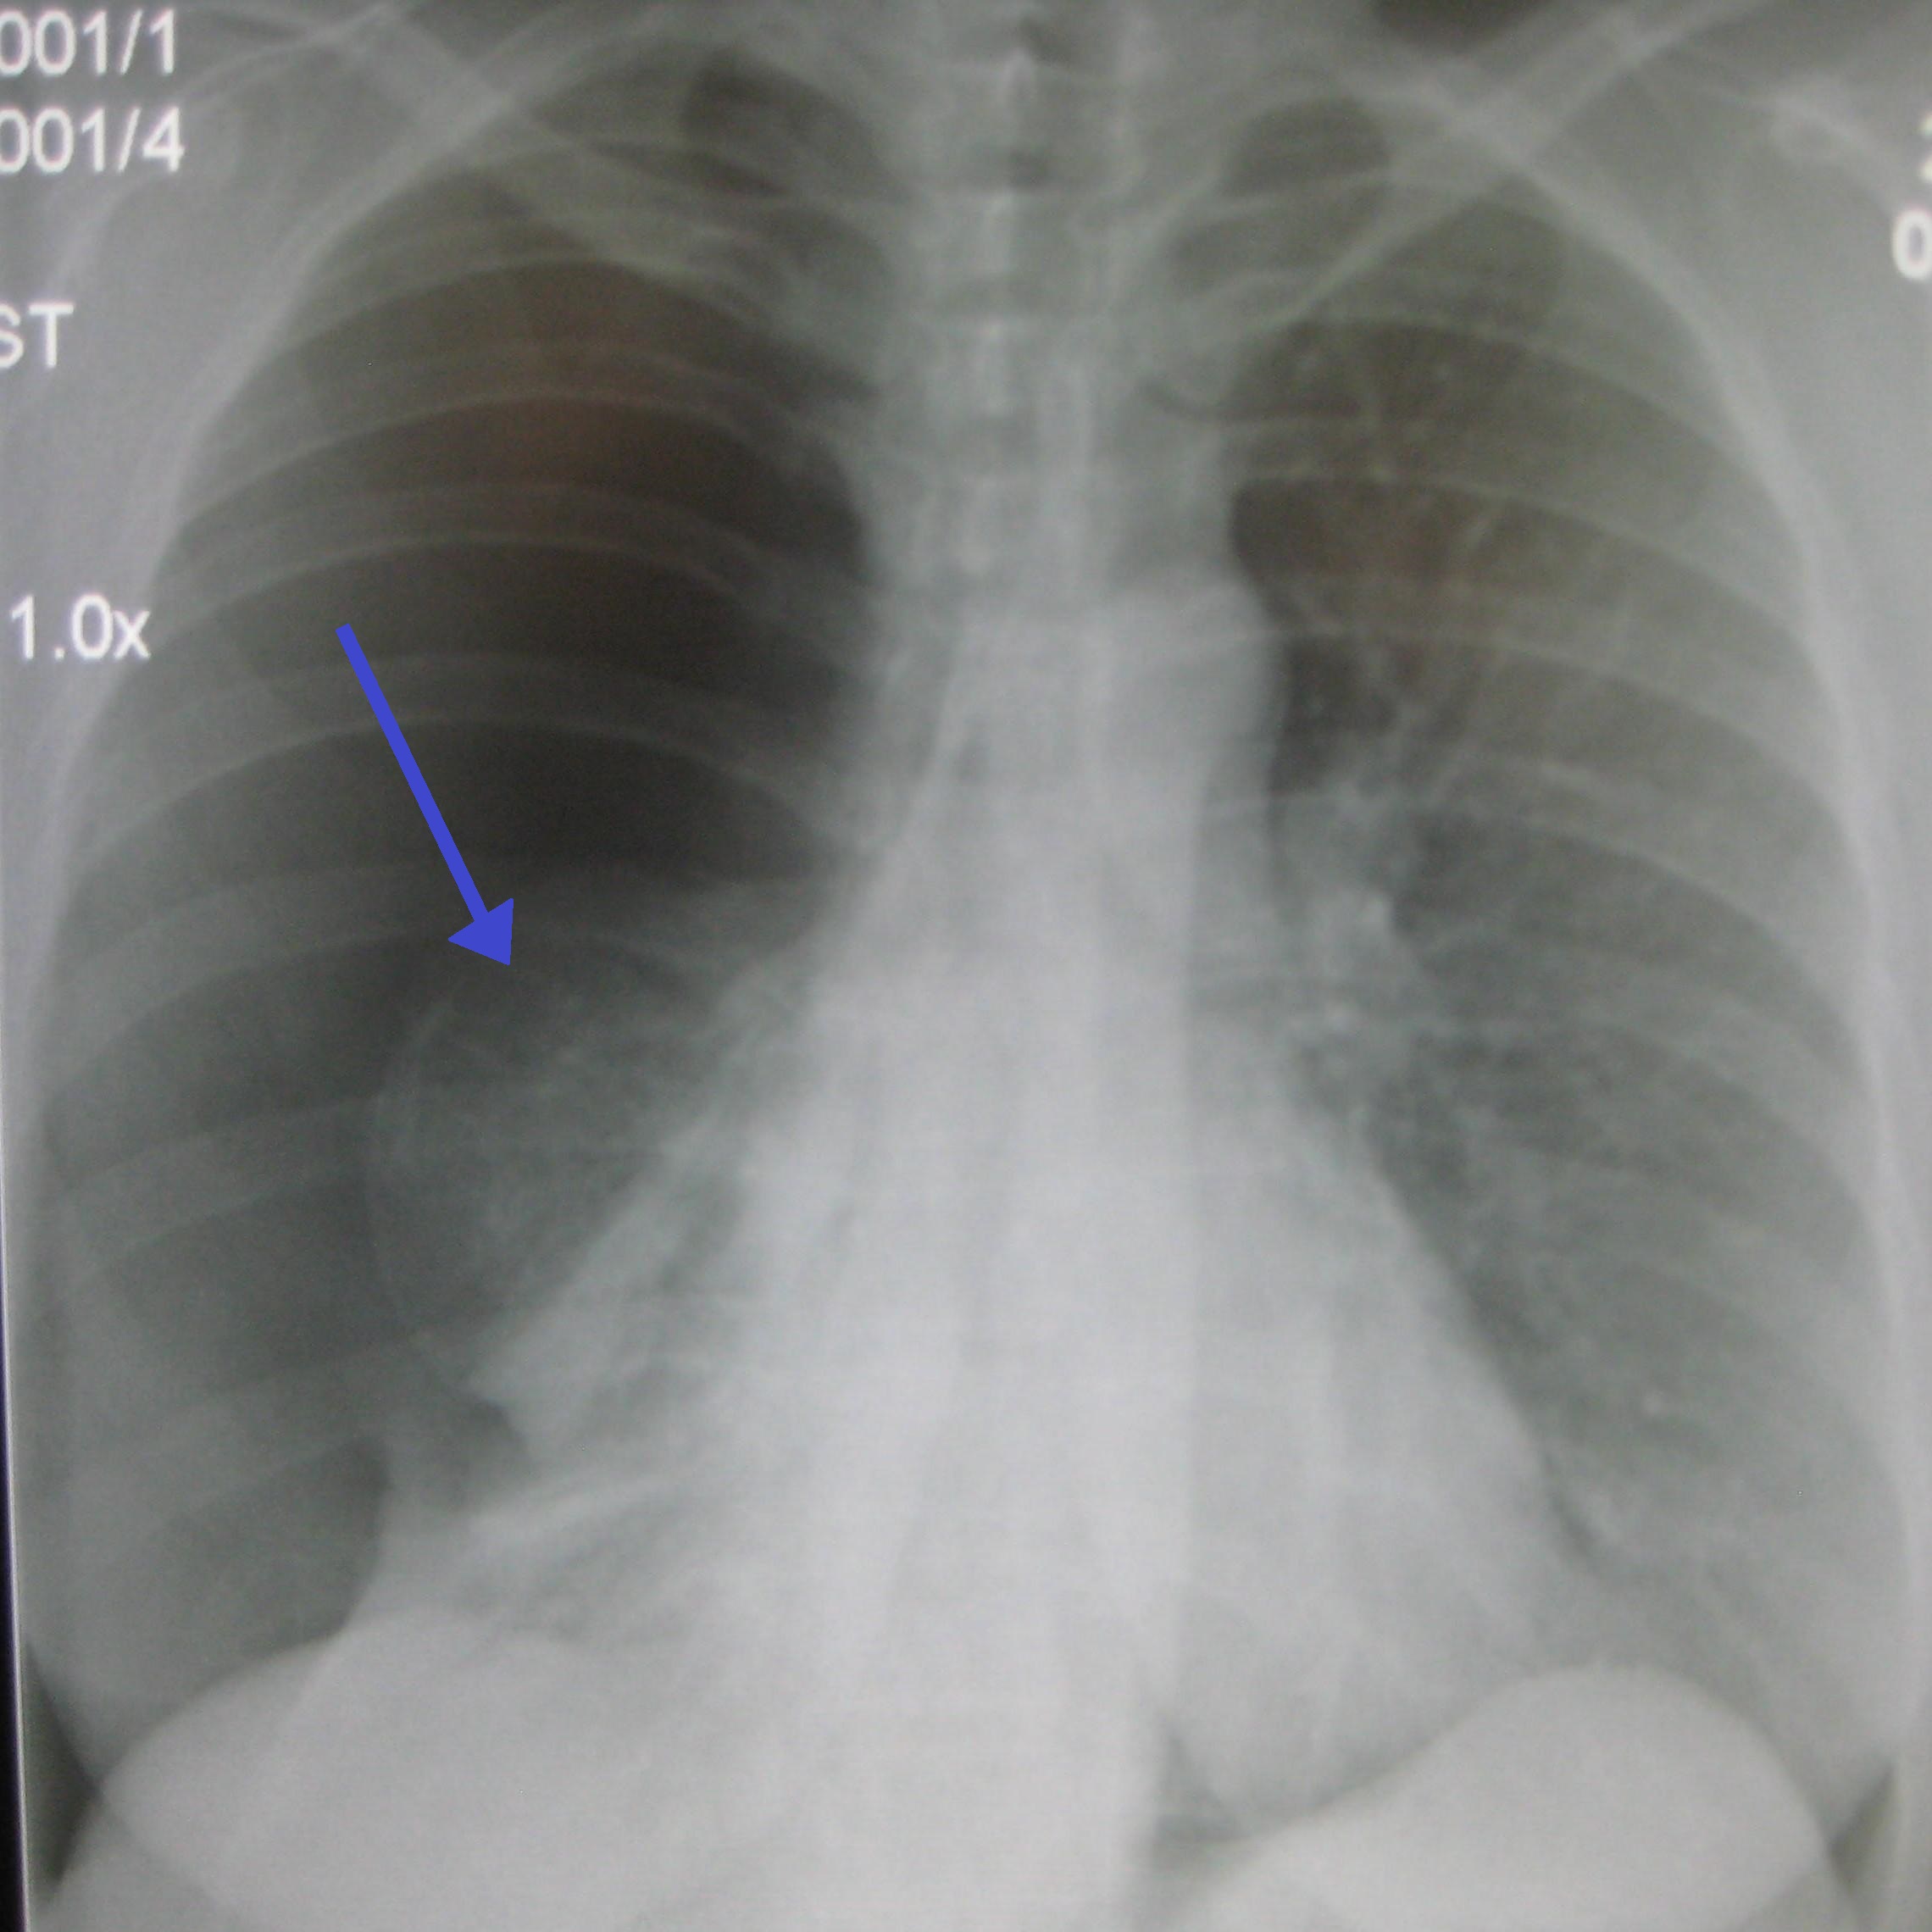

흉부 방사선 사진 촬영으로 진단할 수 있다. 흉부 X선 검사에서 혈관 음영을 동반하지 않는 허탈된 영역은 기흉으로 의심된다.[72] 최대 흡기(숨을 참음) 중에 촬영한 일반 흉부 방사선 사진이 가장 적절한 첫 번째 검사이다.[30] 만기 중에 정기적으로 촬영하는 것은 이점이 없을 것으로 여겨지나,[31] 임상적 의심이 높지만 흡기 방사선 사진이 정상으로 보이는 경우 기흉을 감지하는 데 유용할 수 있다.[32]

기흉의 크기는 흉벽과 폐 사이의 거리를 측정하여 합리적인 정확도로 결정할 수 있다. 2cm의 공기 가장자리는 기흉이 반쪽 가슴의 약 50%를 차지한다는 것을 의미한다.[15]

기흉의 중증도는 다음과 같이 분류할 수 있다.[72]

| 경도 기흉 | 흉부 엑스레이 검사에서, 폐첨(폐의 꼭대기)이 쇄골보다 위에 있다. |

|---|---|

| 중등도 기흉 | 흉부 엑스레이 검사에서, 폐첨이 쇄골보다 아래에 있다. |

| 고도 기흉 | 흉부 엑스레이 검사에서, 폐의 허탈이 현저하다. |

| 긴장성 기흉 | 고도 기흉으로, 더욱이 폐에서 공기가 계속 누출되어, 흉강내가 양압이 되어 있다. |